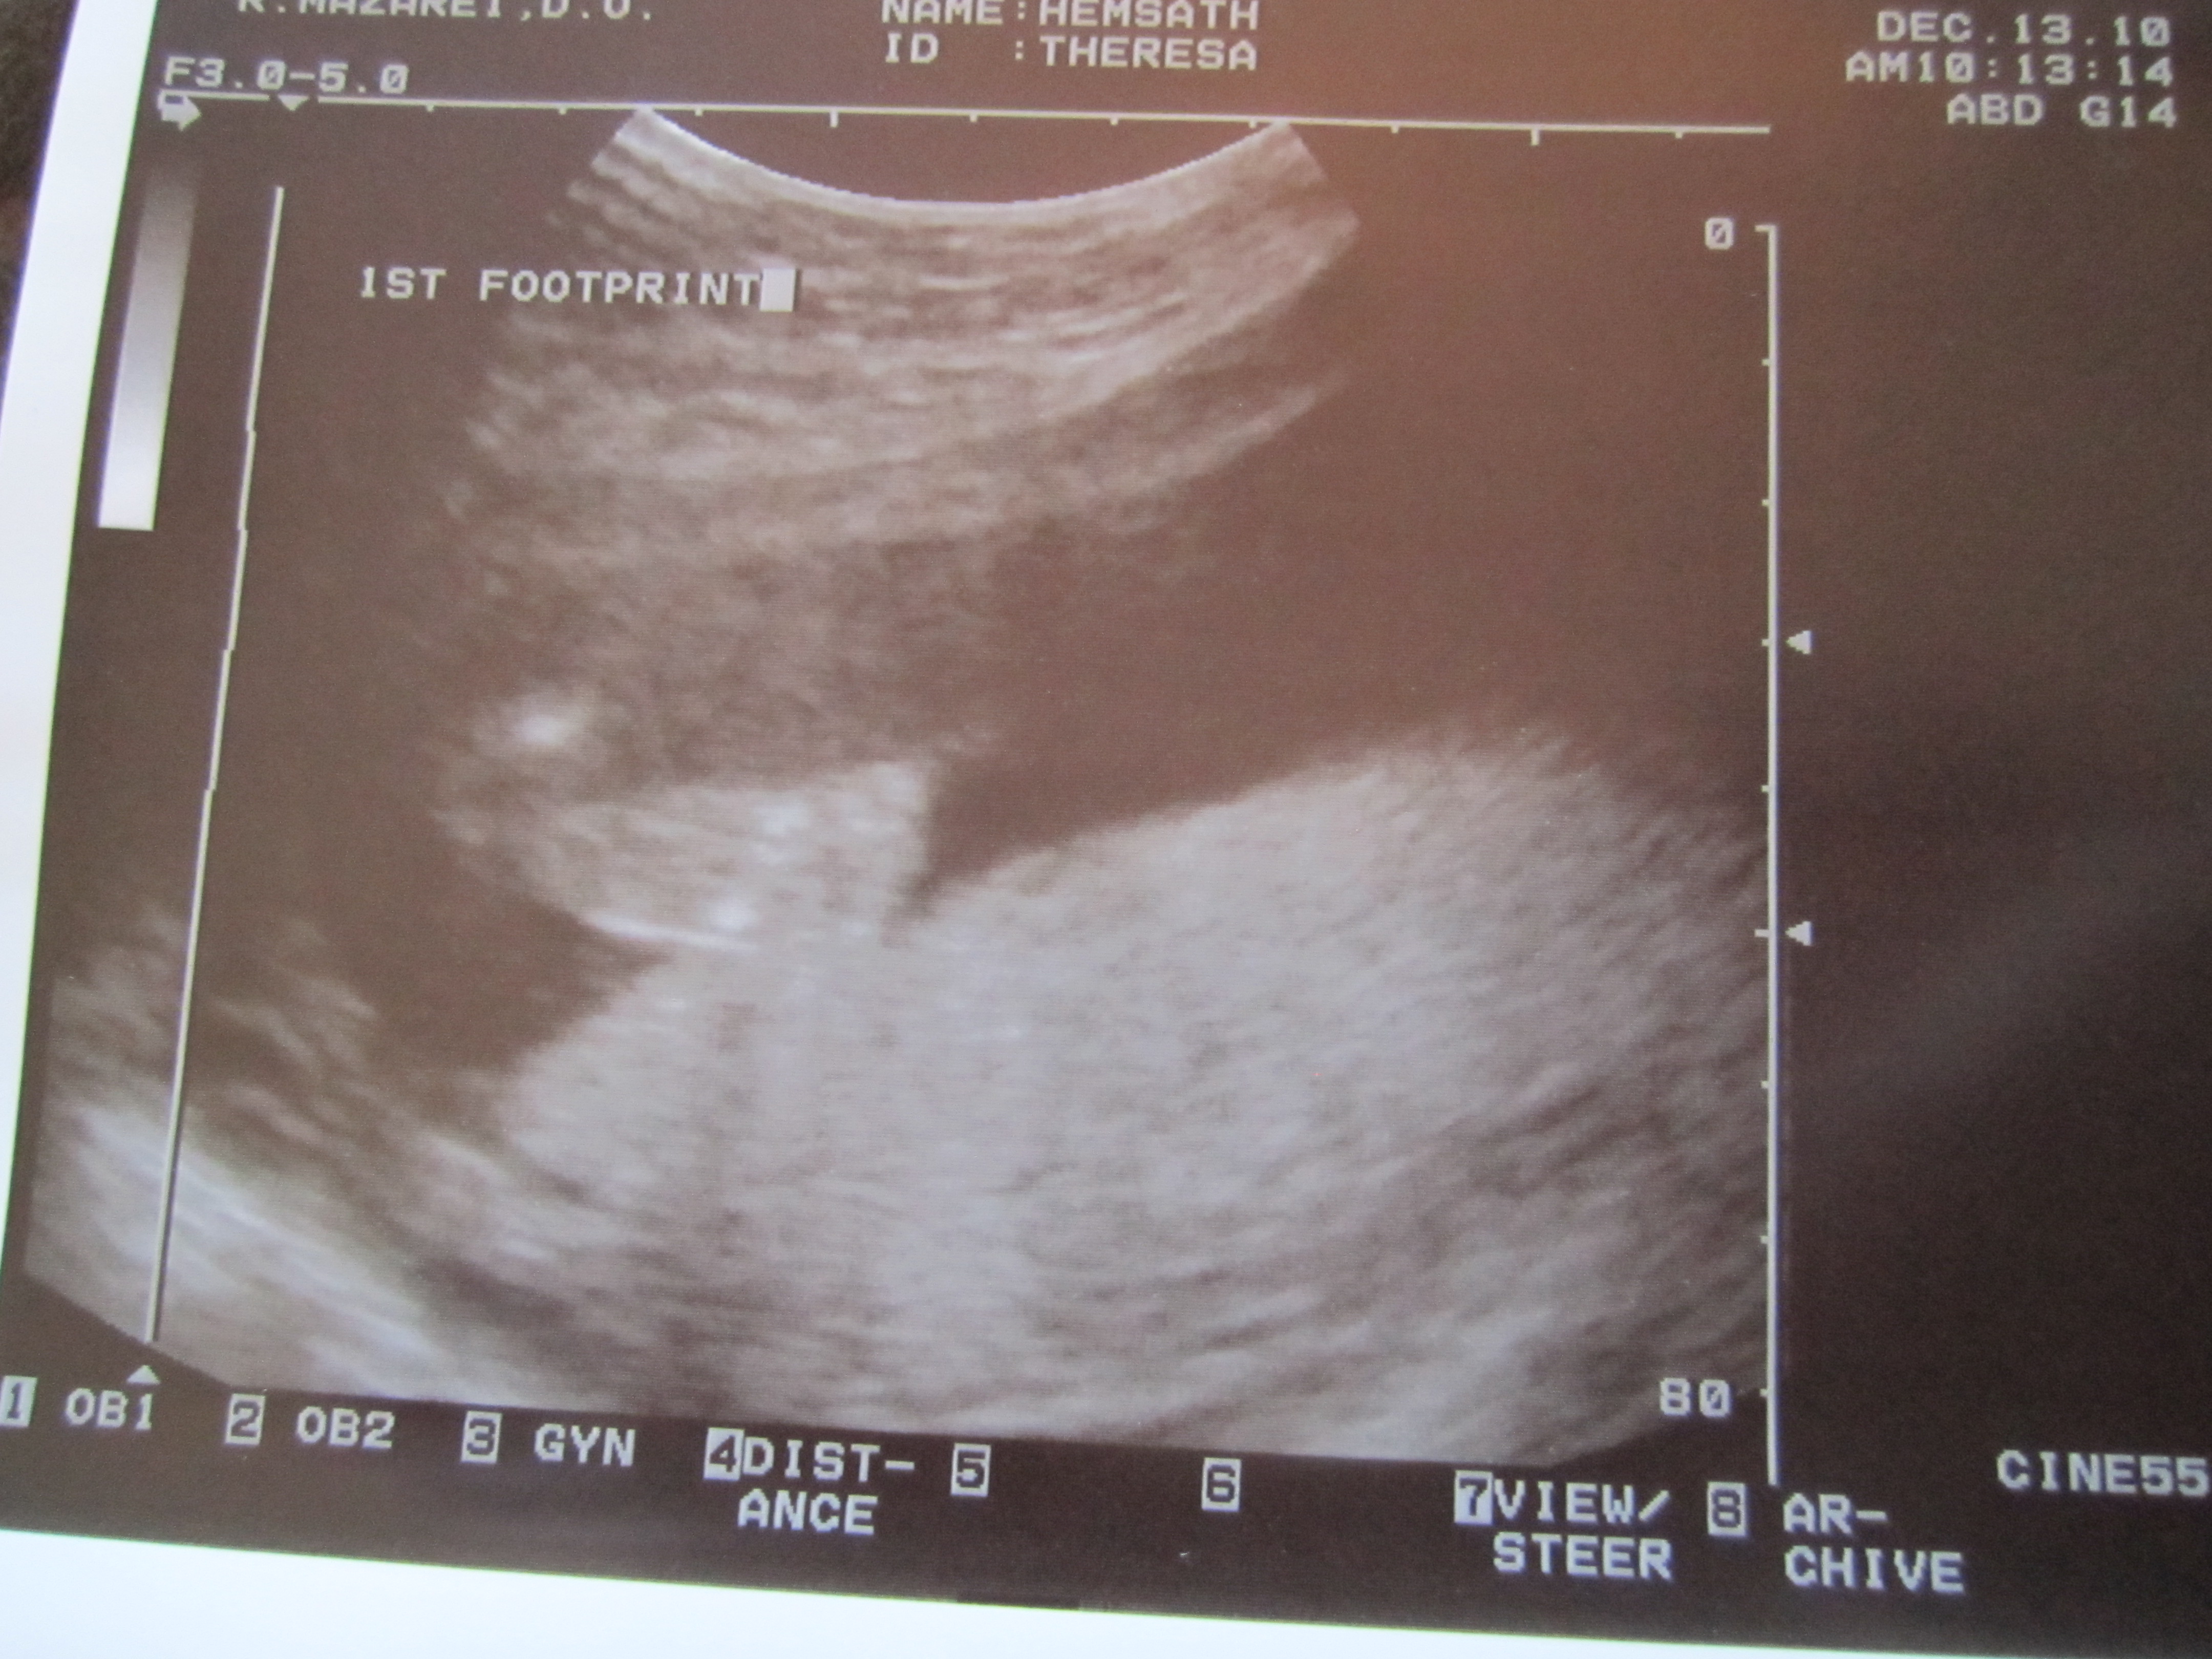

- Talking to Kanan about the baby. He kisses my belly. He tells me he loves his baby brother or sister. He wants him to be a girl and to name her Allison (Even though the ultrasound showed us it is a boy and we think we may name him Mathias or Mateo). He wants me to hold the baby and him or to have Papa (Owen’s name) hold the baby and I hold him. He wants to help feed the baby and hold the baby too. So darn cute! Oh yeah, and he loves watching videos from Baby Center that shows the development of the baby in the womb.

- All the medical scares that come with being pregnant in the 21st century. What ever happened to just being pregnant and having a baby? Now I’ve got to do blood tests and ultrasounds and if anything is slightly off, they scare me with all the what if’s, risks, and possibilities and then want me to do all these other medical procedures. I believe it’s a greedy conspiracy for money.